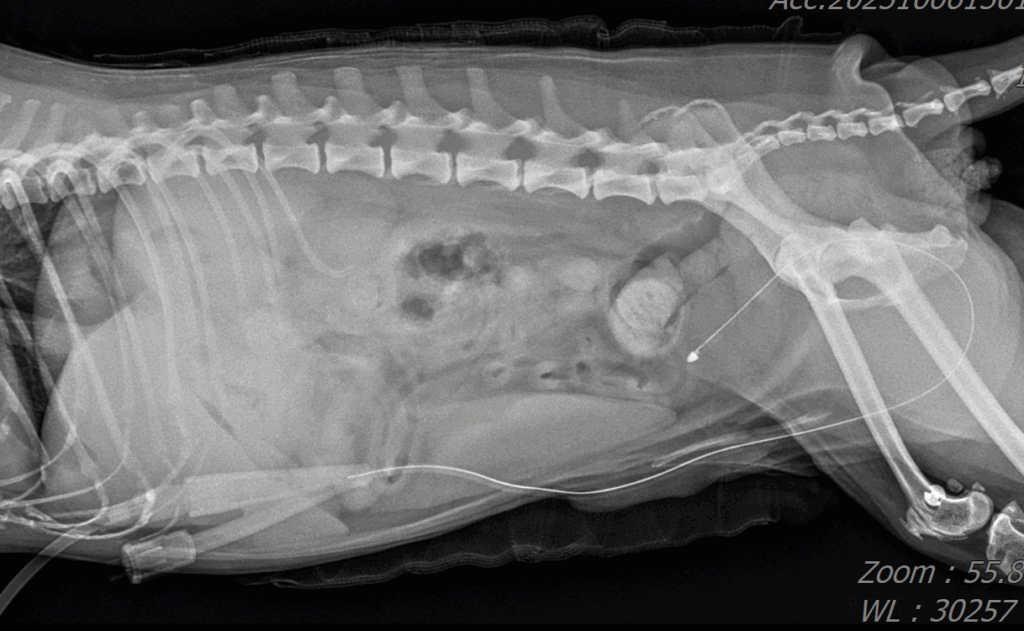

수술 후 방사선 사진 / 출처: 24시 온숲동물의료센터

수술 후 방사선 재촬영 결과, 결석이 완전히 제거되어 방광이 깨끗하게 비워진 상태로 확인되었습니다. 환자는 출혈이나 합병증 없이 안정적으로 회복되었으며, 수액치료와 통증 관리 후 무사히 퇴원했습니다.